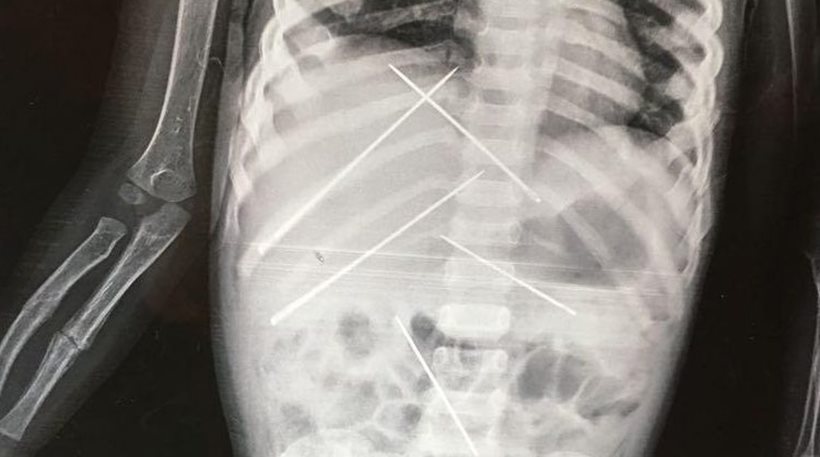

Ειδικότερα, το μικρό παιδί είχε μέσα στο κορμάκι του σχεδόν 10 βελόνες, οι οποίες είχαν χρησιμοποιηθεί πάνω του σε τελετές μαύρης μαγείας.

Όταν υποβλήθηκε σε ακτινογραφία, οι γιατροί αντίκρισαν ένα πρωτοφανές θέαμα. Σχεδόν 10 μεγάλες βελόνες είχαν καρφωθεί μέσα στο σώμα του 3χρονου κοριτσιού, σε διάφορα σημεία. Επίσης, το ένα χέρι του παιδιού ήταν σπασμένο.

Το 3χρονο κορίτσι υποβλήθηκε σε εγχείρηση και της αφαιρέθηκαν οι βελόνες μέσα από το σώμα της.

Όπως αποδείχθηκε από την έρευνα της αστυνομίας, το παιδί είχε υποστεί βασανιστήρια σε τελετή μαύρης μαγείας, από έναν 50χρονο άνδρα ο οποίος εντοπίστηκε και συνελήφθη από τις αρχές. Οι βελόνες βρίσκονταν μέσα στο κορμάκι της για τουλάχιστον 15-20 ημέρες.